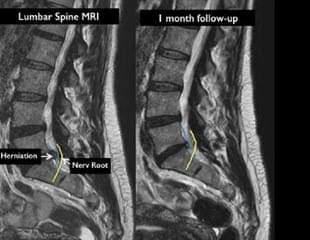

1 -- تیشک ؛ تیشکی ( X-Ray ) ، ( MRI) ، ( C-T Scan ) ۰ ) .